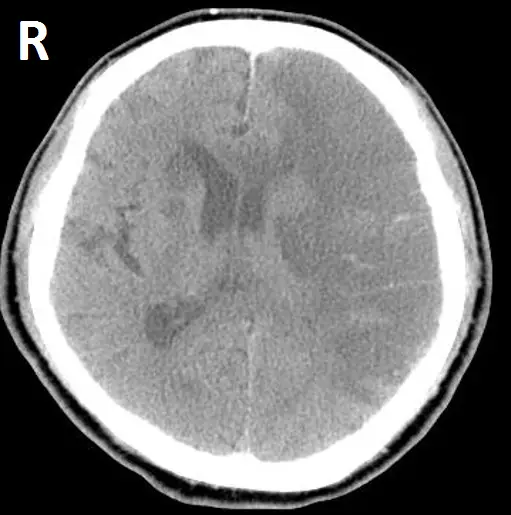

一位 66歲女性病人,有高血壓及心律不整病史多年,被家人發現突然無法言語及右側肢體無力,之後意識逐漸昏迷,其腦部電腦斷層掃描如下,最有可能發生問題的血管為何? 圖片描述

• 影像為非強化腦部CT橫斷面,左側大腦半球(影像右側標記「R」的對側)可見側腦室旁及中央白質區域輕度低密度,而且左側Insular區域灰白質界線消失,呈現「insular ribbon sign」;同時伴有大腦皮質下及皮質區的細微低密度改變,以及左側腦裂隱窩(Sylvian fissure)輕度腦溝壓迫。這些改變反映急性腦水腫與腦實質缺血後的細胞腫脹所致(loss of insular ribbon)(pubmed.ncbi.nlm.nih.gov),並有質子形Hyperdense MCA sign的可能(急性血栓在MCA內呈高密度)(pubmed.ncbi.nlm.nih.gov)。大面積低密度與腦水腫亦可能造成中線結構輕度移位。